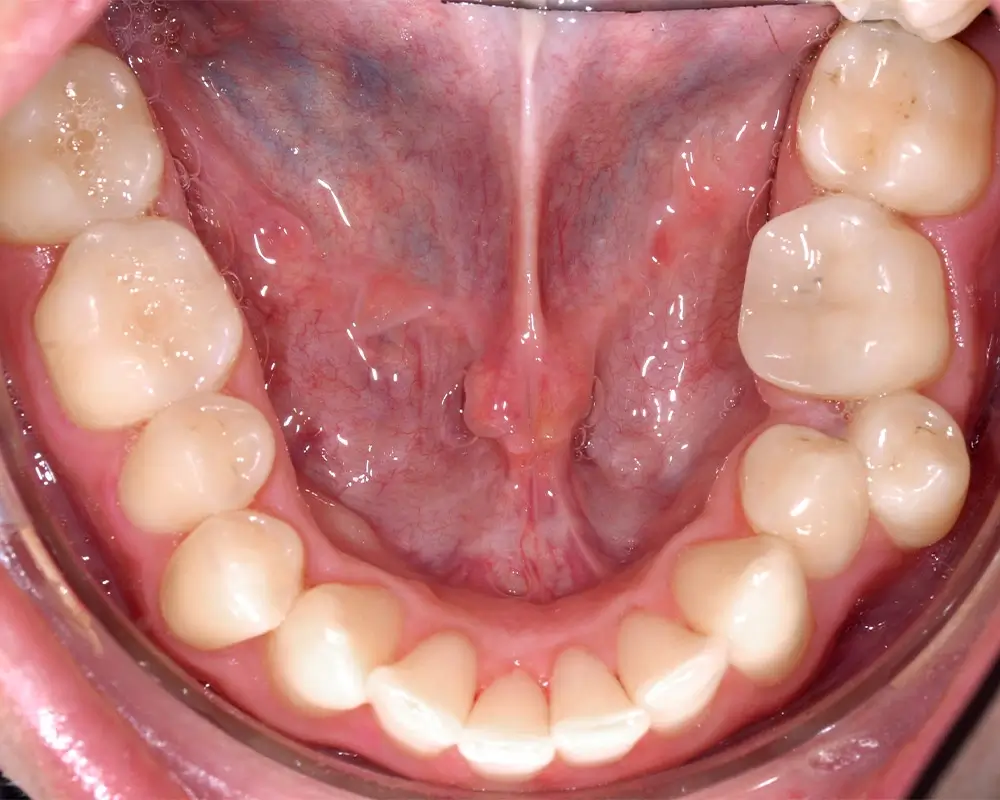

Перекрестный прикус - Кейс 5

Эффективность устранения дефекта прикуса посредством элайнеров FlexiLigner.

27

Количество кап НЧ

25

Количество кап ВЧ

Результаты лечения